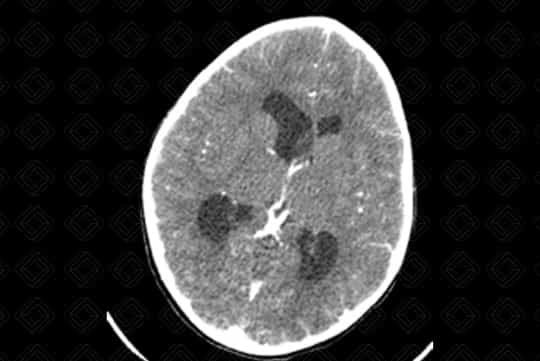

Texto alternativo para a imagem Figura 4. Créditos: Dra. Elazir Mota - Rio de Janeiro/RJ

Descrição das figuras 1, 2, 3, 4 e 5: Tomografia computadorizada do crânio após administração do contraste venoso nas reformatações axial e coronal. Paciente de 4 anos com lesão discretamente captante de contraste (asterisco - figura 2) no corno anterior do ventrículo lateral direito, causando obstrução do forame de Monro e hidrocefalia secundária, de etiologia obstrutiva. [cms-watermark]